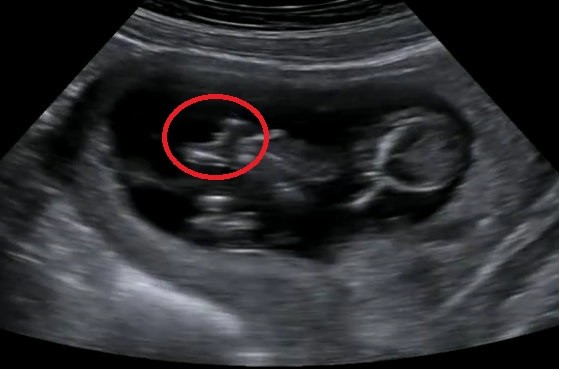

Jest to dla mnie szok ze w 1 cyklu mogą się zrobić 4 nie wiem z czego. Zawsze mi się wydawało ze krwotoczna robi się z ciałka żółtego lub z pęcherzyka. ...... tak mi tłumaczyli wiec nie rozumiem skąd są 4 :errr: Ja też mam teraz 1 krwotoczna 3.5 cm endometrialna 2.6 chyba. Ona teraz na tej kontroli w trakcie antyków ma nadzieję że ich nie będzie i zrobi Ci start jak znikną a jak nie to przedłuży antyki. Mi pomaga naproxen i maść z niedźwiedzia na plecy i rozchodzic

Jakie duże te krwotoczne. ?

Jakie duże te krwotoczne. ?[/QUOTE/]

Chyba cos ok 3 cm ale glowy nie dam, nie pamiętam. Za dlugi dzien dziś. Jeszcze wieczorem bylam na usg piersi.Kurde od paru dni tak mnie bola ze masakra. Nawet koszulka sprawia ból :( mam po jednej torbieli w kazdej piersi ale malutkie ok 1 cm.A bola przez te wszystkie hormony.